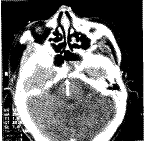

经鼻蝶入路显微手术修补床突-斜坡部缺损所致脑脊液鼻漏

斜坡部脑脊液鼻漏较少见 ......